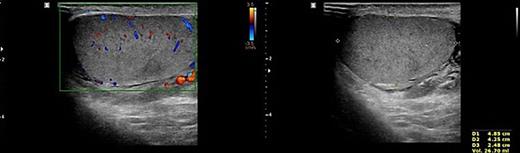

Doppler ultrasonography of the patient. No other abnormality except mild fluid collection was shown on the left testis and epididymis.

To prevent the patient from further self-injury, simple therapeutic restraint of both arms was performed with the patient’s consent, and sedative medication was administered. He was closely observed in the intensive care unit to monitor his hemoglobin and systemic conditions. Additional transfusion treatment was provided as needed. Psychiatric medicines including antipsychotics and sedatives (Clozapine 125–250 mg/day, haloperidol 2.5–5 mg, and lorazepam 1–2 mg/day) were prescribed by a psychiatrist. After 5 days of taking the psychiatric medication, the patient no longer reported the impulse to harm himself, and was able to release the simple restraint on both arms. No further self-harm occurred until he was discharged, presumably due to the proper effects of taking psychiatric medication. Anticoagulant agents (5 mg apixaban, twice per day), subcutaneous heparin injection (5,000 IU, twice per day), and alprostadil (10 mg, once per day) were given for circulation to prevent the thrombosis of vessels. On POD2 from the first operation, a testicular scan with technetium pertechnetate revealed the viability of the remnant left testis compared with the amputated right testis (Fig. 7). On POD4, contrast-enhanced CT showed the enhancement of the vessel into the testis (Fig. 8). On POD7, scrotum Doppler ultrasonography revealed the Doppler signal in the parenchyma of the testis (Fig. 9). Testosterone levels increased after the surgeries and normalized on POD5 (Fig. 10). He was discharged on POD9 without any skin complication (Fig. 6c). After discharge, he returned to our clinic for follow-up on POD13 and 23. On the visit, laboratory follow-up including testosterone and free testosterone was checked and confirmed as normal (Fig. 10).

We performed five examinations to check the viability of the replanted testis. First, in the operating room, we used indocyanine green after replantation (Fig. 4). Indocyanine green fluorescence perfusion showed testicular perfusion, which enabled the immediate checking of the viability of vessels. This procedure is appropriate for checking the viability of microscopic vessels that may be damaged during a milking test. Second, a testicular scan showed the viability of the testis (Fig. 7). One testis is markedly different from the lesion of orchiectomy. However, the scan resolution was low because of a wide range of arterial courses and the disturbance of the urethral catheter or bladder. Third, contrast-enhanced CT displayed the vascularity of the testis and the surrounding parts (Fig. 8). However, the shooting time to the enhanced phase could affect the failure of the vascularity of the testis. No protocol for this case has been established in our institute; therefore, CT was a nonspecific tool for testicular examination. Fourth, ultrasonography efficiently showed the vascularity inside the testis (Fig. 9). However, skin wound could inhibit or limit ultrasonography. Fifth, we indirectly checked the testicular function based on testosterone levels (Fig. 10). A laboratory examination should be performed continuously. However, this procedure could be limited among hypogonadal men, and the separate testicular function of each testis could not be easily identified. Nevertheless, these techniques will help determine the viability of the testis in specific situations.